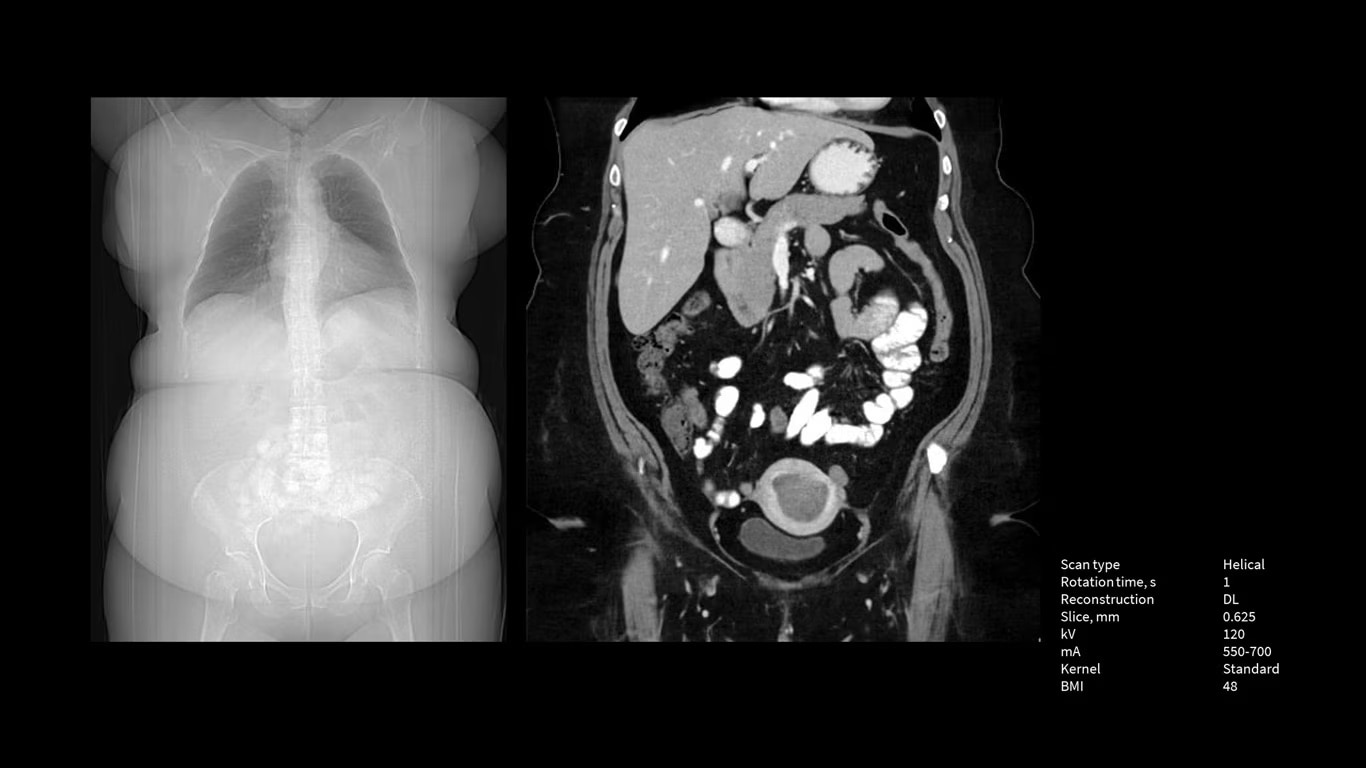

Power like never before

The Revolution Apex platform provides high power output. The ability to upgrade means that siting challenges no longer prevent you from high power output to your department. If your siting power is limited to 150 KVA in the initial installation, you can start with the Power Pro option at maximum 1200 mA, and later on, you can scale up to 1300 mA Power Xtream when you upgrade the powerline.